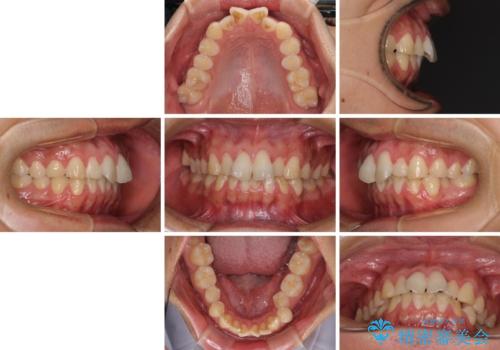

- 上下前歯のデコボコと、それに伴う出っ歯を気にして来院された患者様です。

インビザラインによる上下歯列の側方拡大と後方移動、IPR(歯と歯の間を削る)にるスペースの獲得により歯列を整えることとしました。

歯と歯の間を削ることでうまくスペースコントロールでき、また、毎日22時間以上しっかりとマウスピースを装着していただいたので、スムーズに治療が進みました。

治療途中で転勤となり、遠方からの通院となったため、来院間隔空いてしまいましたが、2年間で終えることができました。